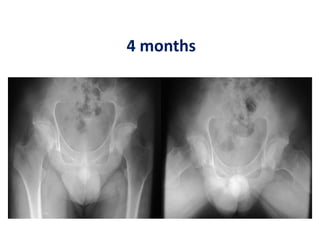

Case 2- hip 3 – 4 months

Case 2- hip3 – 4 months